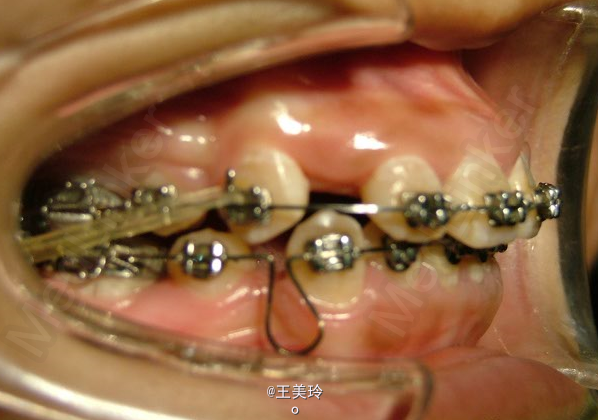

主诉:面突求矫治 既往史:无矫治史,无牙科治疗史,无外伤史,无过敏史,无口腔不良习惯,无家族遗传史 口腔检查:恒牙列,A7-B7;C7-D7。个别牙齿不齐 尖牙磨牙I类关系轻度深覆合深覆盖 下颌中线右偏约2mm 双颌前突,突面型 关节无弹响无压痛

诊断:安氏I类双颌前突 矫治计划 1.MBT矫治技术 2.拔牙矫治,拔A4B4C4D4 3.闭隙曲,J勾内收前牙 4.矫治结束后尖牙,磨牙,覆合覆盖正常 5.面型有所改善